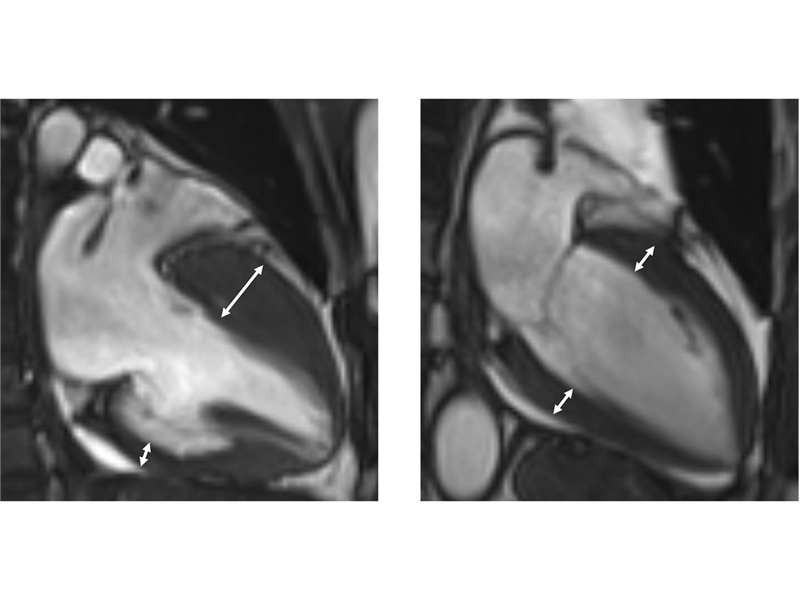

▲비후성 심근병증을 가진 환자의 자기공명영상(왼쪽). 좌심실전벽의 두께가 심실 후벽에 비해 현저히 두껍다. 정상 심장 자기공명영상(오른쪽)의 경우 좌심실 전벽과 후벽의 두께가 동일하다.

진단은 심장초음파, 자기공명영상 등 영상검사를 통해 이뤄지며, 비후된 심근 내에 섬유화가 진행돼 있거나, 근육조직이 지방조직으로 변성이 돼 있는 상태가 관찰된다. 하지만 이 같은 조직변성이 없는 비후성 심근병증도 있는 만큼 전문의의 종합적 판단이 중요하다.